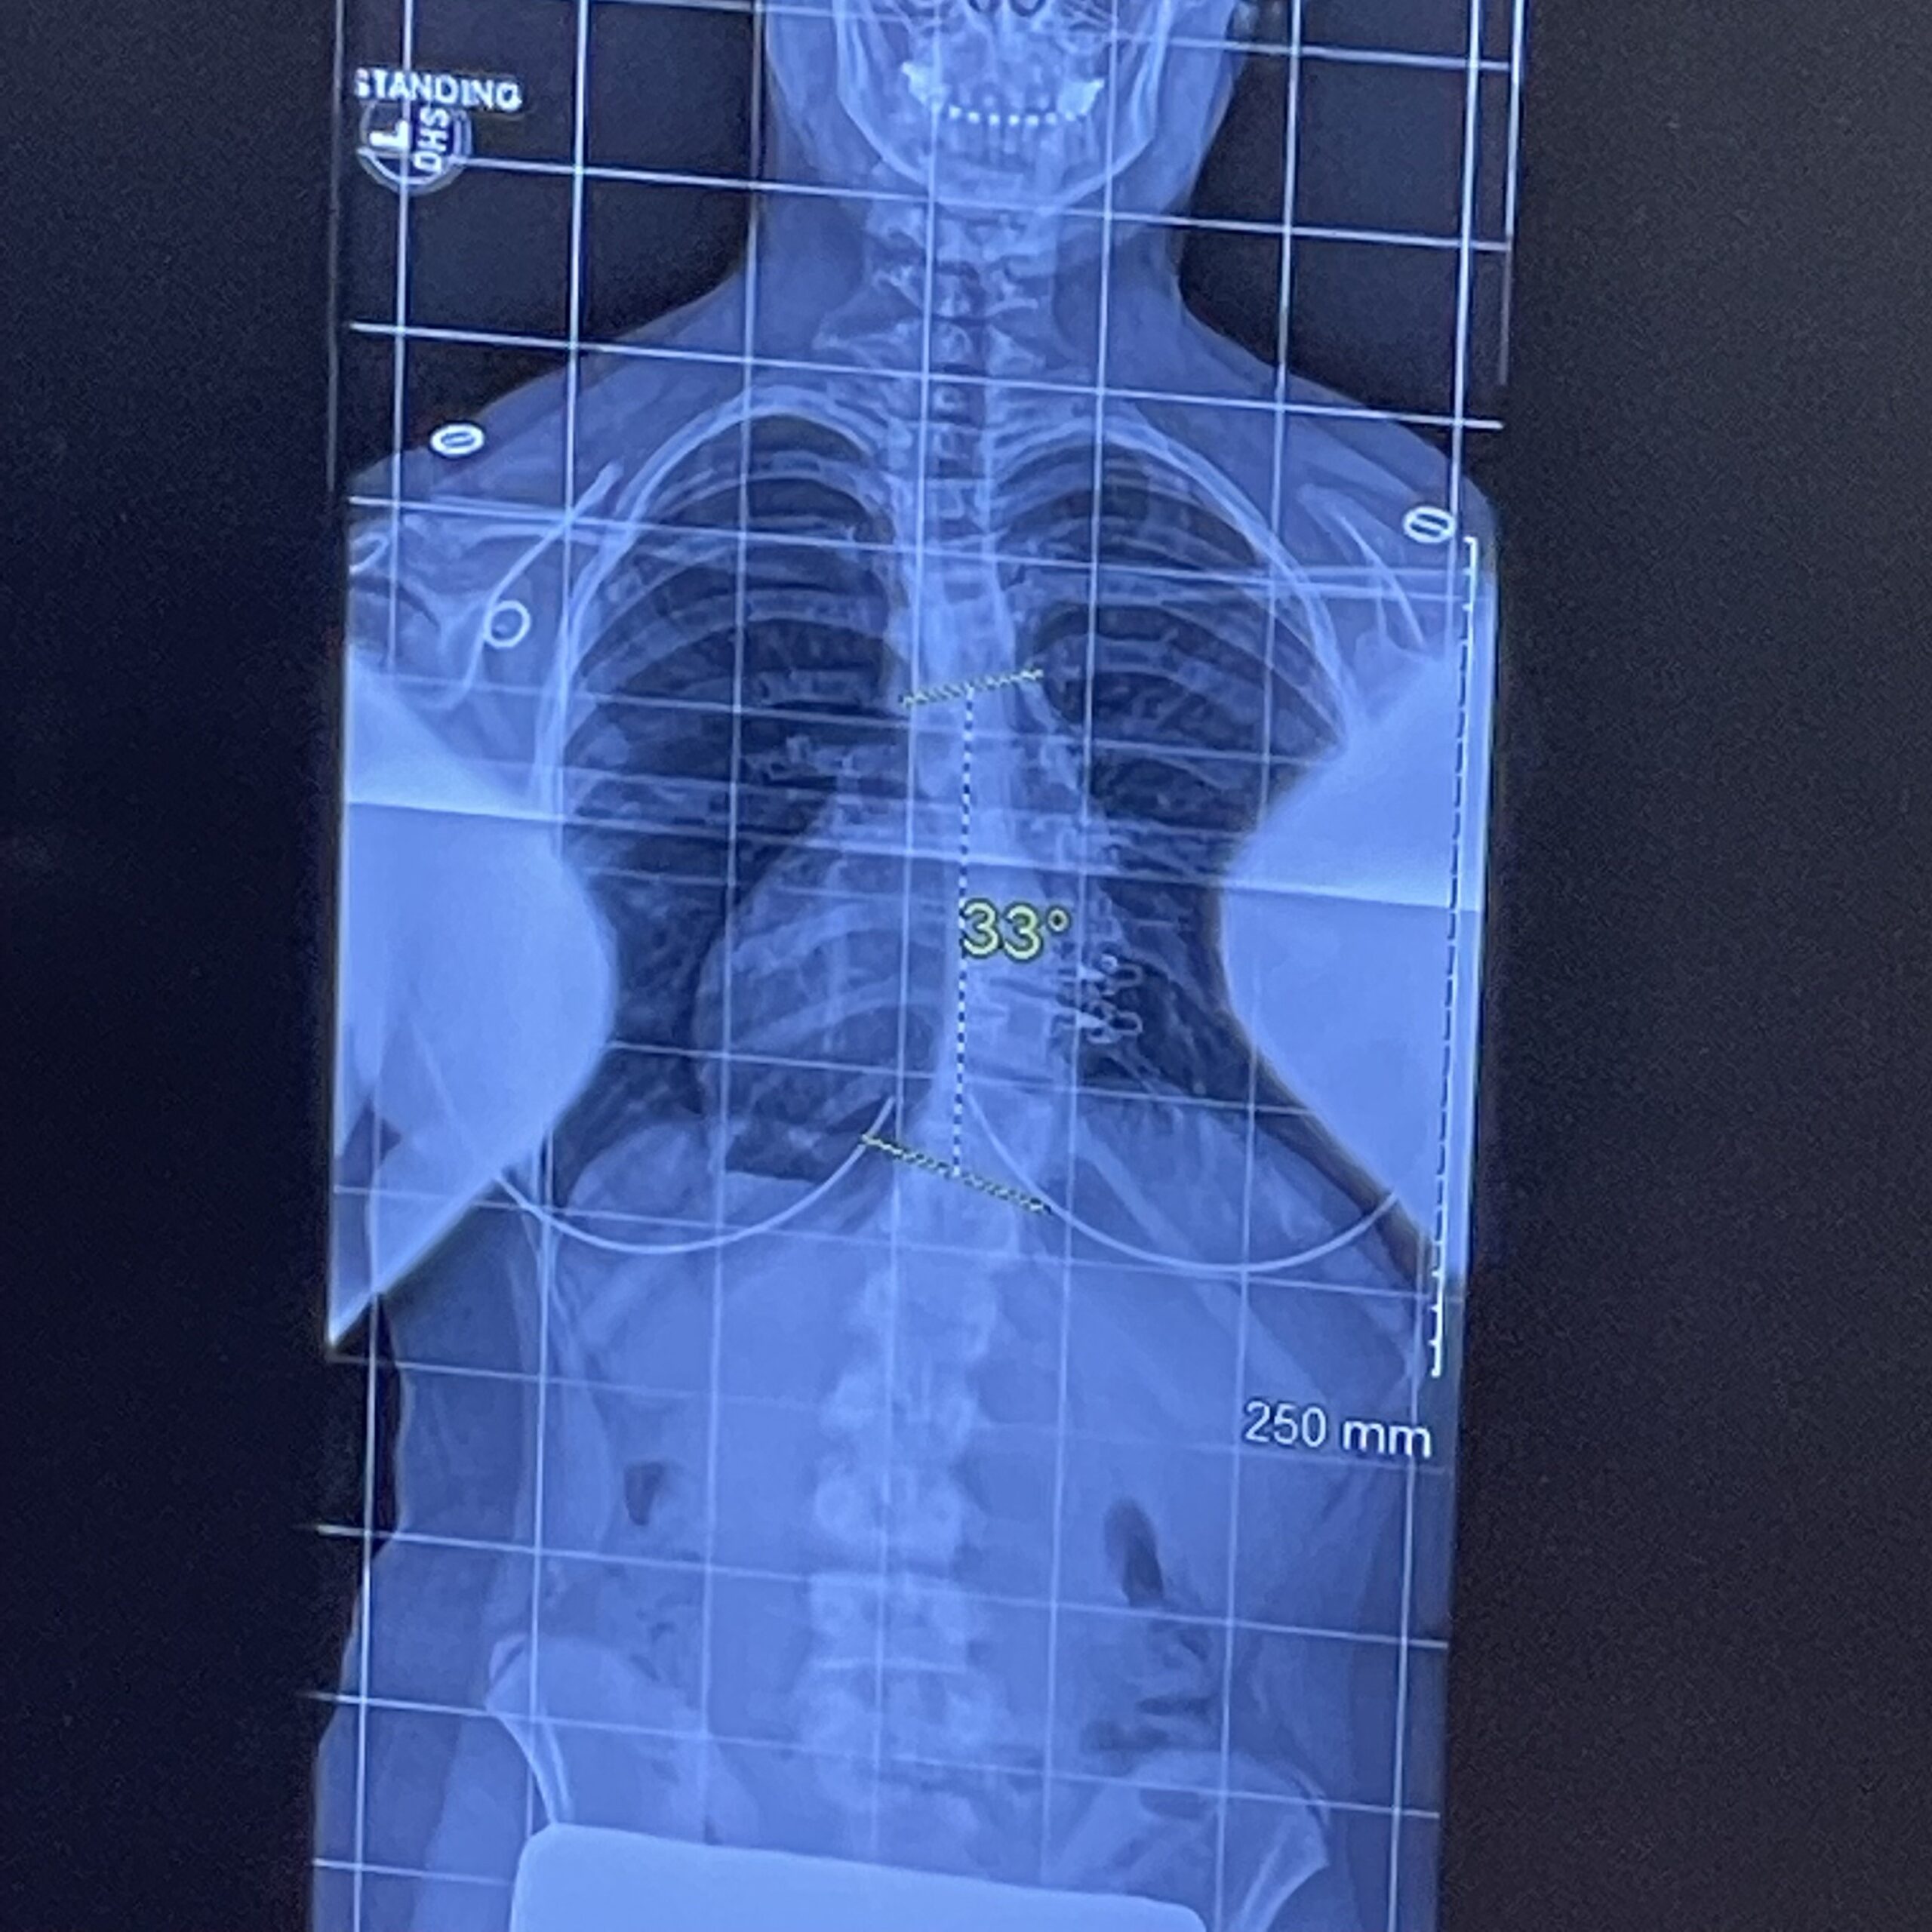

When I was first diagnosed, my top curve measured 33 degrees. By the time I was released, it had progressed to 43 degrees on top and 31 degrees on the bottom — despite 3 years of bracing. My doctor told me that scoliosis can continue to progress, even into adulthood, and that staying active and practicing Schroth would be lifelong tools to help manage it.